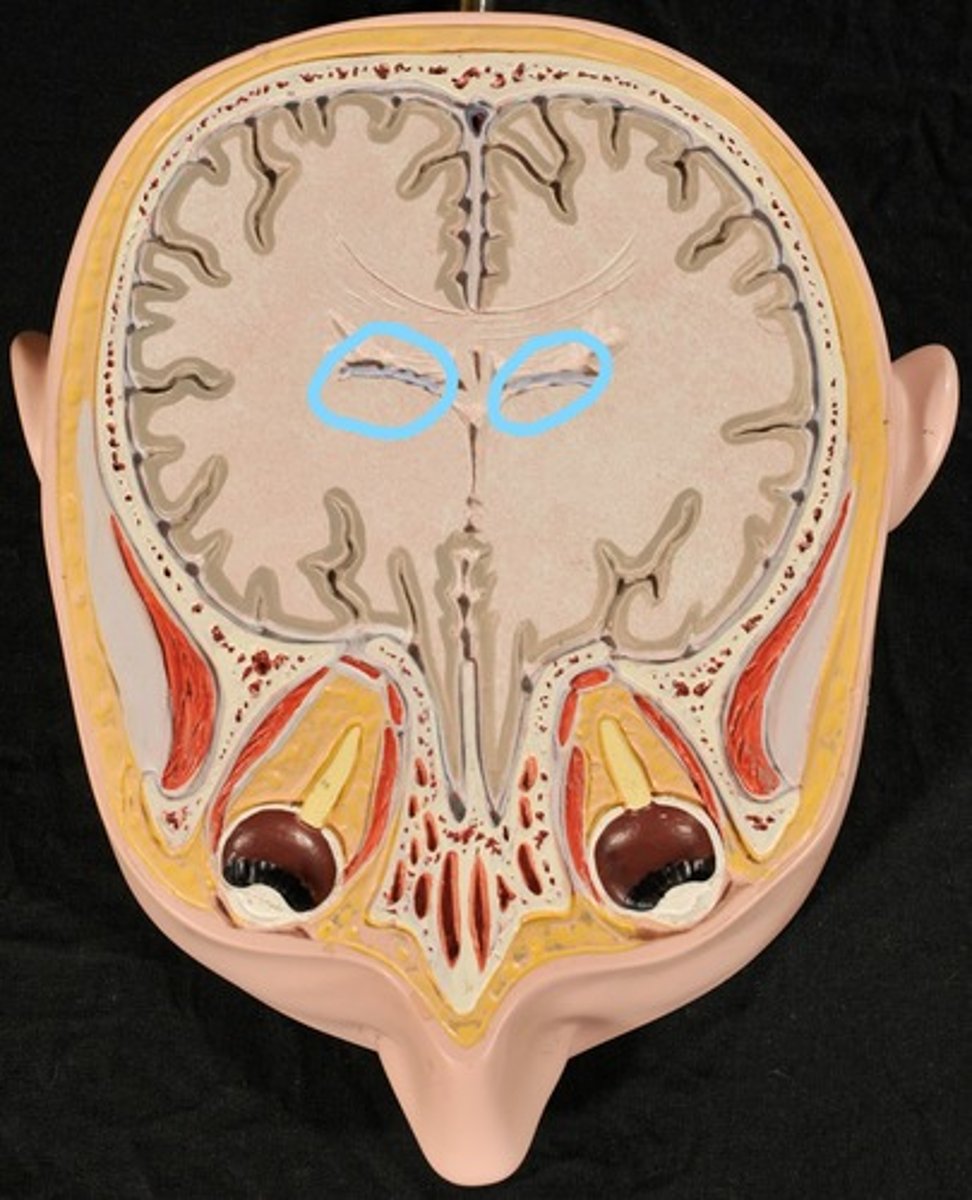

Choroid Plexus (blue) (Slice 2)

Right & Left Lateral Ventricles (Slice 2)

Third Ventricle (Slice 2)